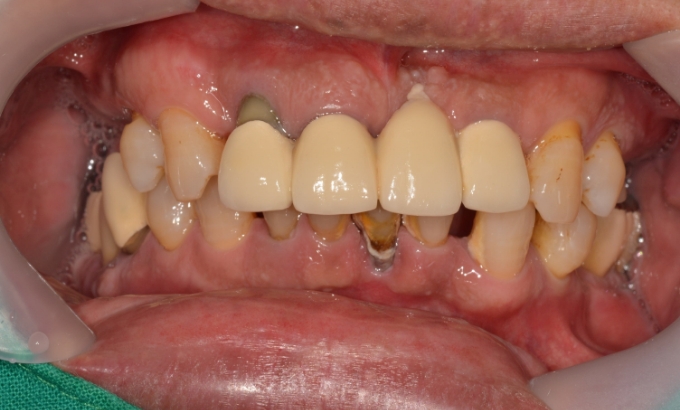

01

2018. 01. 02 ~ 2020. 02. 12

간단한 증례는 아프지 않게 임플란트를 식립합니다.

Before